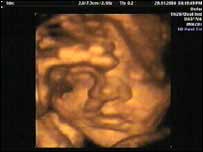

A bouncing baby girlClare and Steve similarly felt overwhelmed by the pressure of trying again for a child. Thankfully they tried again. At 31 weeks pregnant, a scan showed a clear image of their unborn baby's face and even predicts the birth weight. "After everything we've been through, I can't believe we've seen the face of our unborn child," says Steve. | Sources of help and support | The Miscarriage Association c/o Clayton Hospital Northgate Wakefield West Yorkshire WF1 3JS